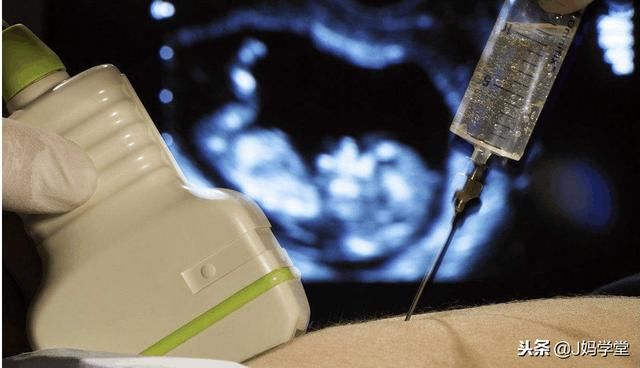

2.接受羊膜透析

这是一种用于检查某些遗传问题的产前检查,通常在16周左右,这也能发现她们是生男孩还是生女孩。这种检查通常在35岁或35岁以上的母亲身上进行,包括在子宫内插入一根针,以取出少量羊水。然而,这项测试并不是没有风险的,也不是简单地为了确定宝宝的性别而进行的。